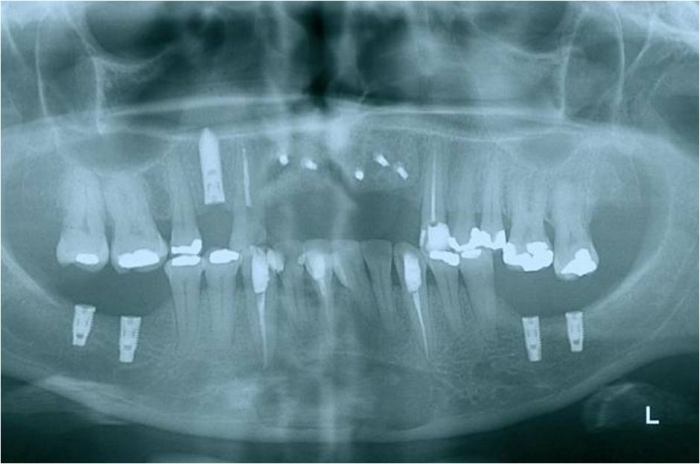

Raio x após enxerto ósseo e implantes